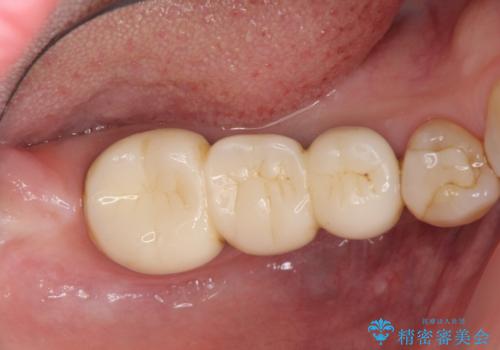

咬合痛の原因となっている右下第2大臼歯の根幹治療を行ったのち、強度に優れるフルジルコニアクラウンによる咬合機能回復を計画します。

- 28.6万円(仮歯・フルジルコニアクラウン×3・ファイバーコア)費用は治療当時の料金となります